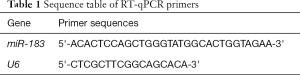

Serum miRNA-183 expression detection by quantitative real-time polymerase chain (RT-qPCR)

Early in the morning, 4 mL of blood was drawn from patients who had an empty stomach. Samples were centrifuged at 2,500 r/min, centrifuged for 10 min, and then serum was collected from the centrifugal tube. Serum total RNA was extracted with a whole blood RNA extraction kit (AM1836, Thermo Fisher, USA). Total RNA was reverse transcribed into cDNA, using DNA fluorescent SYBRGreenIto test the expression level of miRNA-183, with U6 as the reference gene, in 40 cycles at 60 °C for 10 min, at 95 °C and 72 °C for 30 s, and at 95 °C for 5 min. Experiments were repeated three times, using 2−ΔΔCT expression of miR-183 for calculations. The primer sequences are shown in Table 1.

Full table

The changes of miR-183 levels in peripheral venous blood in each group

Peripheral blood samples were collected from 138 patients with CIRI and 60 healthy volunteers, and the expression of miR-183 in serum was detected by RT-qPCR. As shown in Figure 2, compared with the control group, the expression level of miR-183 in the peripheral blood of patients with CIRI was significantly higher (P<0.01).

Increasing attention has been paid to the application of miRNA in clinical practice. The brain tissue is rich in miRNA, with more types and higher expression levels of miRNA than in other organs. The expression of miRNA in the brain is closely regulated, and the expression of miRNA has fixed sequences and regions during the development of the brain (15). When the body is geomagnetic, miR-183 exists in sense organs, and when cancer, neurological disorders, or autoimmune disorders occur, miR-183 has a higher expression in the non-sensory organs. In etiology research and target therapy, the use miR-183 and some associated factors has gradually increased for the diagnosis, prevention and treatment of CIRI (16). miR-183 also exhibits specific expression in the human and mouse cerebral cortex, affecting the development of the cerebral cortex and regulating the differentiation of nerve cells. For example, after dorsal root ganglion injury in adult rats, the expression of miR-183 was significantly decreased, and its distribution was closely related to stress granule (SG) protein, suggesting that the regulation of chronic neuralgia by miR-183 could be realized through pain-related genes (17). Yuan et al. (18) found that miR-183-5p increased in the hippocampus under chronic and persistent mild mental stress, indicating that the increased miR-183-5p level was associated with stress-induced depression. Meanwhile, miR-183 was demonstrated to interfere with glucose and lipid metabolism, and its abnormal expression has been related to metabolic diseases like obesity and diabetes, and it has been shown to induce cerebrovascular diseases, such as atherosclerosis (19). In this study, RT-qPCR detection found that, compared with the control group, the level of miR-183 in peripheral blood of patients with CIRI was significantly higher than that of the control group. Meanwhile, the level of serum miR-183 in the CIRI group was positively correlated with the increase of imaging lesions. These results confirm that miR-183 is involved in the occurrence and development of ischemia-reperfusion. MiR-183 can inhibit the activation of microglia and the expression of inflammatory factors through NF-κ-signaling pathway (20). Down regulation of miR-451 can promote angiogenesis by targeting macrophage migration inhibitory factor in hypoxic human umbilical vein endothelial cells, indicating that miR-451 is a potential candidate for the treatment of cerebral ischemia injury (21). SNHG1 targets miR-199a and up regulates SIRT1 expression, thus alleviating cerebral ischemia/reperfusion injury through AMPK pathway activation (22).